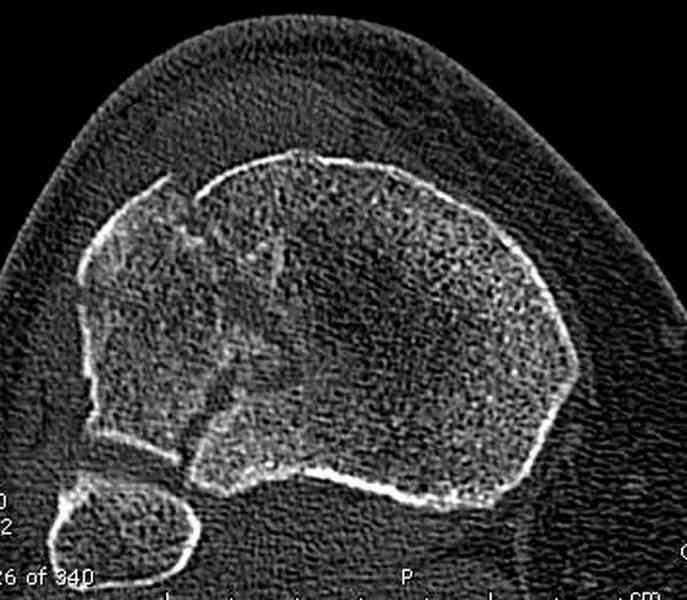

Касаемо перелома мыщелка, лучше сделать СКТ и после определиться с операцией. Фиксировать - проксимальной поддерживающей пластиной. Есть хорошие варианты. Чтож до дистальной части - аппарат кроме стабилизации ничего не даст. Если 6 кг вытяжения не расколотили отломки, то при открытом доступе вся эта мелочь вывалится. По-моема операцию следует рассматривать с позиции подготовки к артродезу (ось выправить, осколки попытаться собрать). Ну и готовить морально пациентку к неработающему голеностопу.

Для внутрисуставных переломов необходимо идеальное сопоставление, а такая задача без КТ срезов усложнится. Только КТ надо делать после дистракции сустава, иначе нельзя получить объективную информацию.

Репозиция внутрисуставных переломов неудовлетворительная и не адекватна.

сценарий и для перелома наружного мыщелка б.б.- передний фрагмент стоит на месте, а задний не репонирован - в таком положении оставлять фрагменты нельзя, суставная поверхность должна быть реконструирована.